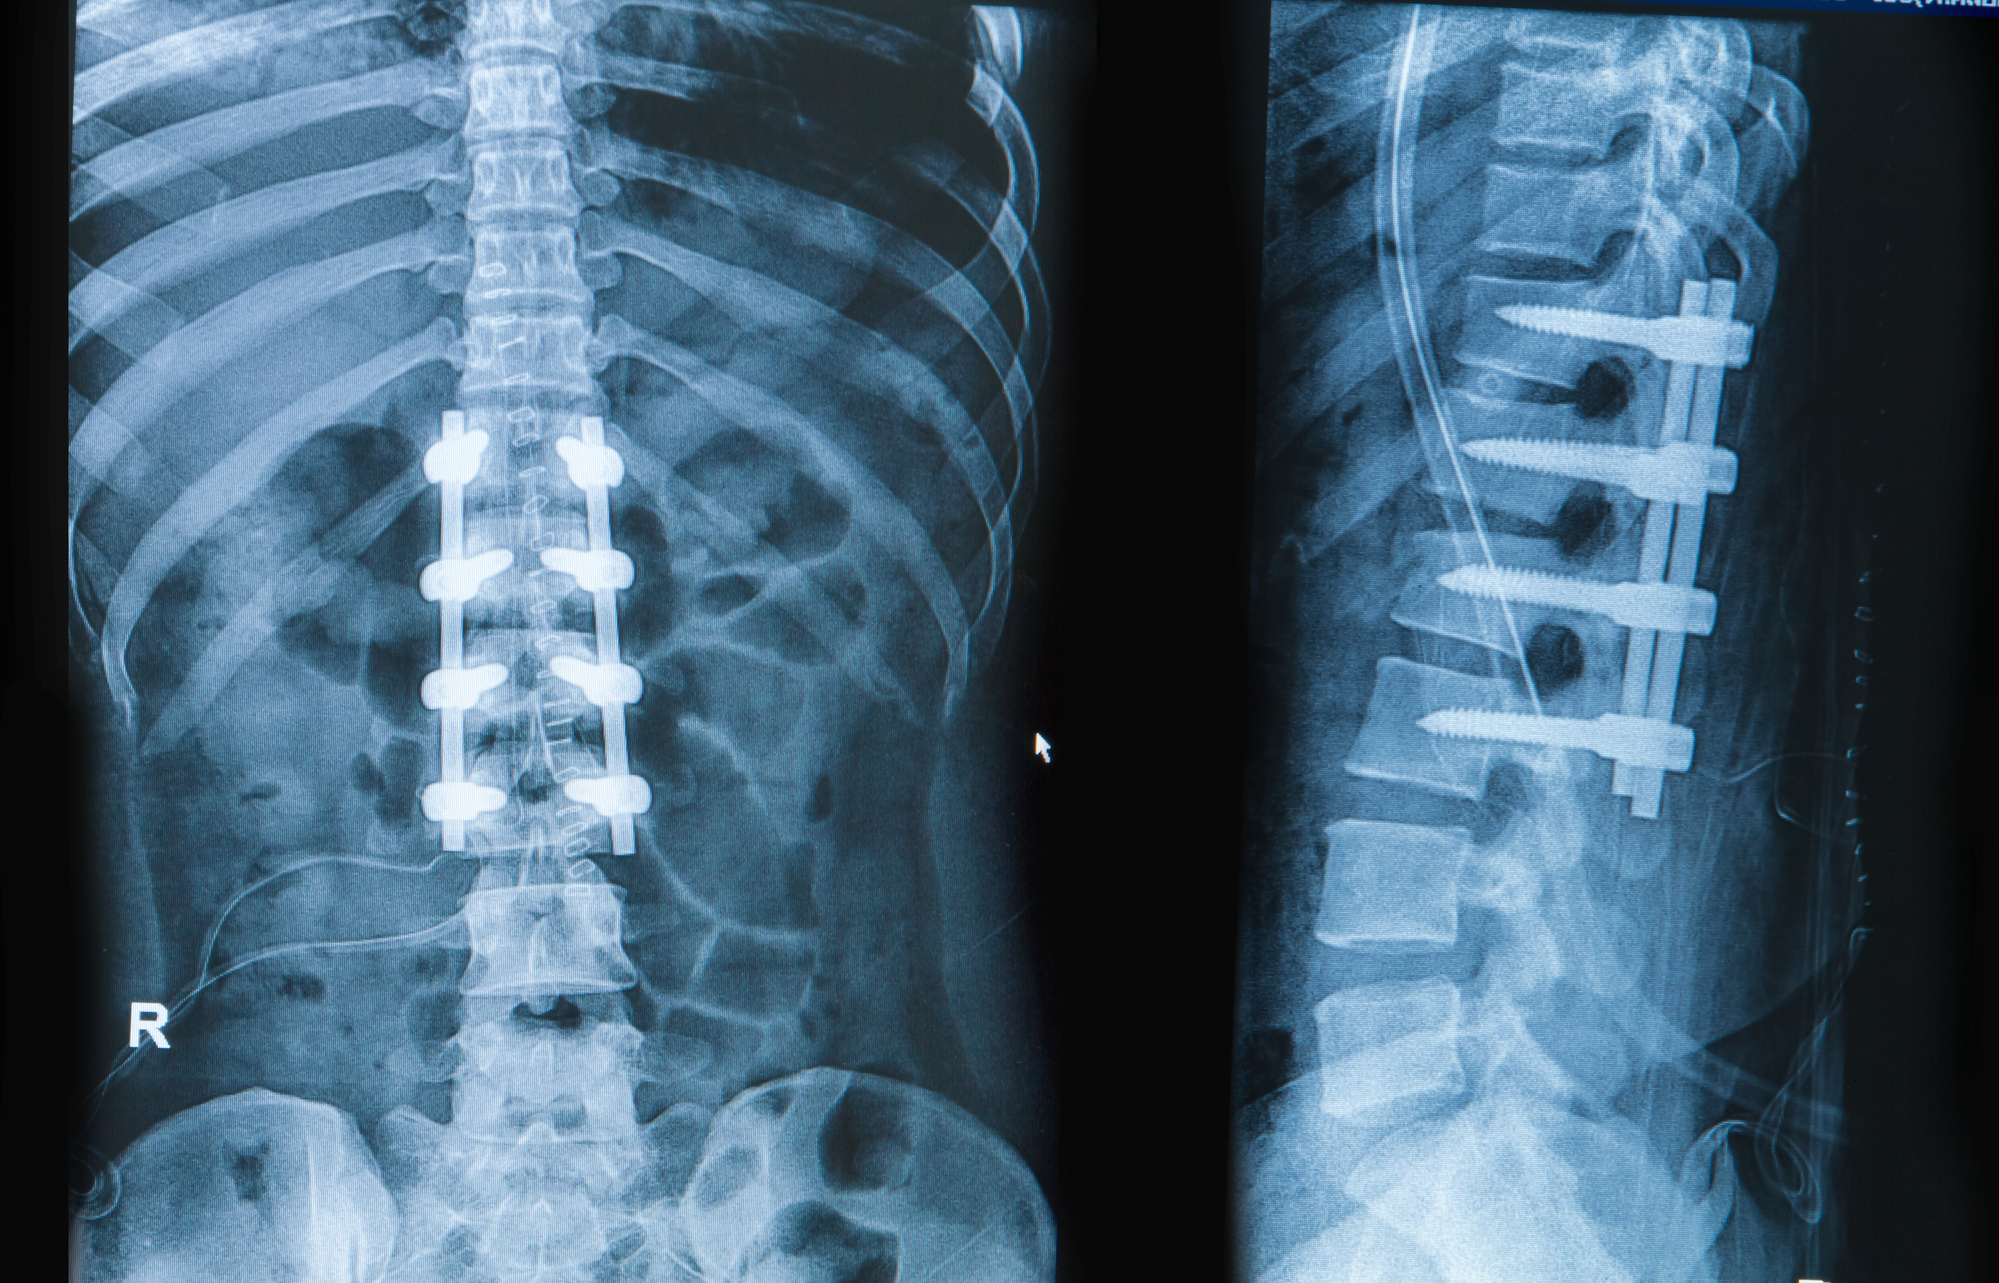

As the initial acute healing subsides, typically around the three-month mark, the focus begins to shift gradually toward regaining function and preparing for formal physical therapy. “Nutrition plays a surprisingly pivotal and direct role in optimizing the fusion process itself” underscores the link between diet and bone health. While the ‘BLT’ restrictions often remain, the intensity of movement increases, usually with the start of an outpatient physical therapy program. This is a highly individualized process, tailored to the patient’s fusion status—verified by X-rays—and specific surgical approach. Therapy initially concentrates on establishing core stability, improving gait mechanics, and performing gentle stretches to counteract the muscle atrophy and stiffness resulting from prolonged immobilization. The goal is to build a robust muscular corset around the spine to offload stress from the newly fused segments, a critical step toward long-term pain reduction and functional improvement.

The six-to-twelve-month window after surgery is generally when the most dramatic return to functional activity occurs, provided the fusion is radiographically confirmed to be solid. “As the initial acute healing subsides, typically around the three-month mark, the focus begins to shift gradually toward regaining function and preparing for formal physical therapy” highlights the start of formal physical therapy. At this point, many patients are cleared to return to work, even those in jobs requiring light physical activity, and can begin to reincorporate recreational activities. However, the absence of movement in the fused segment necessitates a permanent awareness of body mechanics to prevent excessive strain on the adjacent, unfused vertebral levels. This new biomechanical reality requires a conscious modification of everyday movements—using hips and knees to bend, pivoting the entire body rather than twisting the torso—to minimize the risk of developing adjacent segment disease over time, a common long-term complication.